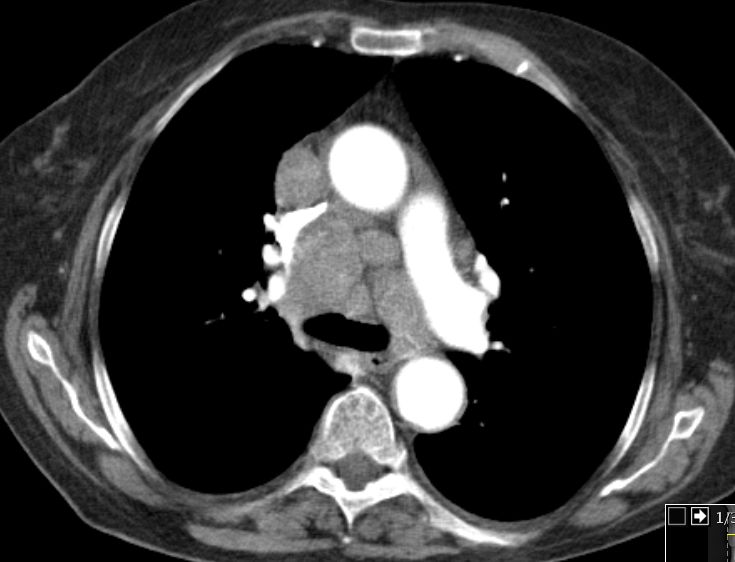

Auch im Mediastinum große LK-Metastasen.